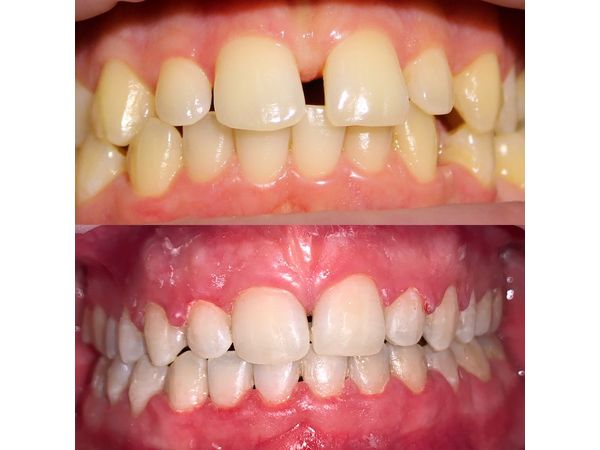

Трансверзальная резцовая окклюзия (смещение средней линии зубов вправо). Аномалия положения зубов. Вторичная адентия (потеря 25 и 35-го зубов).

Пациенту провели санацию полости рта. Чтобы выравнять положение зубов, ему установили самолигирующую брекет-систему Damon Q, в которой ортодонтическая дуга фиксируется с помощью специальных замков. Полнопазная дуга 19×25 из высококачественной нержавеющей стали закрыла щель в области отсутствующих зубов.

В итоге мужчине выравняли зубы, создали правильную форму зубных дуг, закрыли все щели и добились того, чтобы верхние и нижние зубы находились в нормальном положении относительно друг друга.